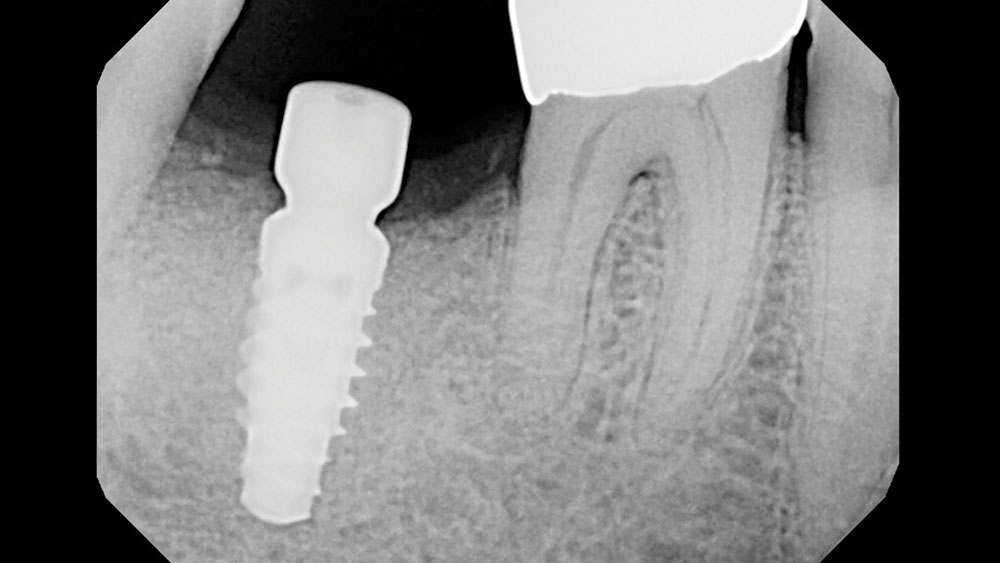

Following well-established clinical research methods, bone loss was measured as the distance from the implant shoulder to the first contact of bone to implant, from both the mesial and distal sides.

Figures 1a, 1b: Calibration of the bone loss measurements was determined by measuring the length of the implant (1a), or by measuring the diameter in cases where the implant apex was not visible (1b).